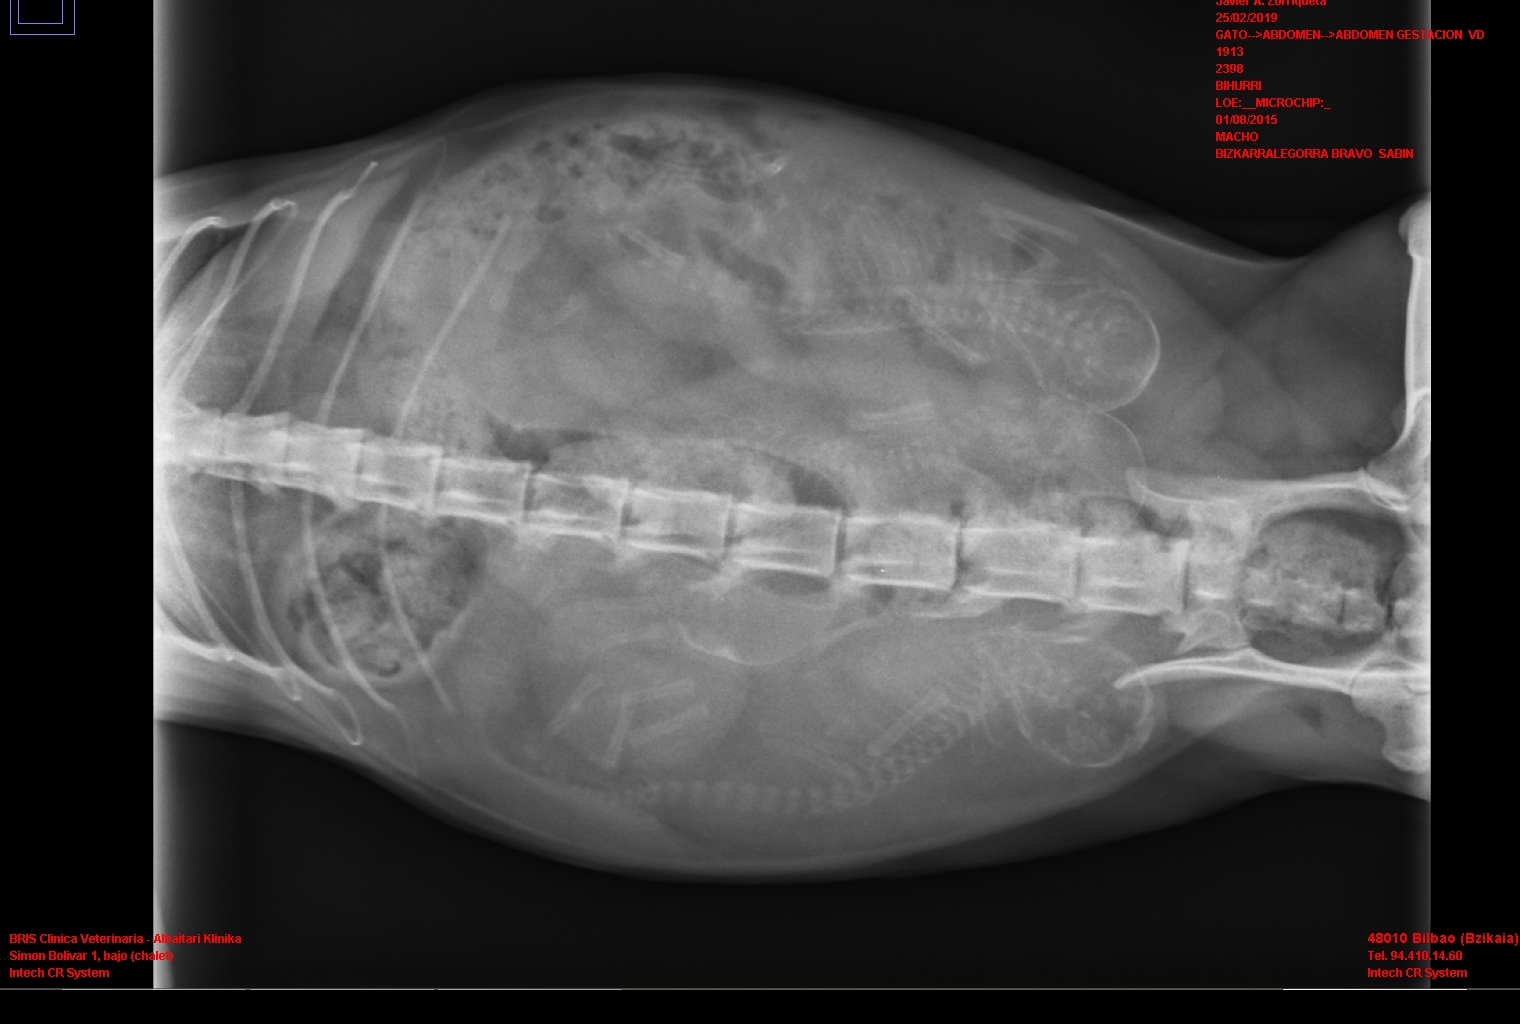

Día de gestación 58

L. 25-2-2019

Las imágenes de rayos-x se observa que las crías están desarrollándose correctamente.

Bihurri (2d)+ las 4 crías

Bihurri (2d), las 4 crías